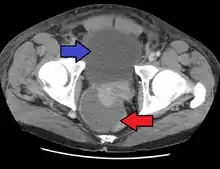

Severely ill patients may need hospitalization, while nontoxic patients can be treated at home with bed rest, analgesics, stool softeners, and hydration. Men with acute prostatitis complicated by urinary retention are best managed with a suprapubic catheter or intermittent catheterization. Lack of clinical response to antibiotics should raise the suspicion of an abscess and prompt an imaging study such as a transrectal ultrasound (TRUS).[7]